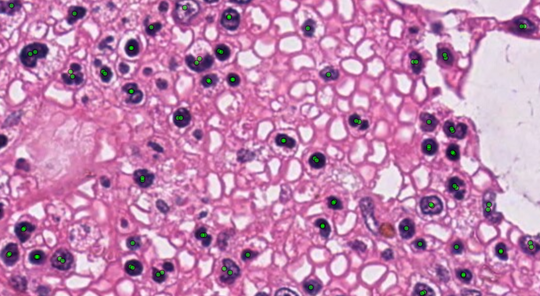

Digital histology is being increasingly used in research and clinical applications. In parallel, new tissue imaging methods (e.g., imaging mass spectrometry) are currently regarded as very promising approaches for better molecular diagnosis in pathology. However, these new data sources are still often underexploited because of the lack of collaborative software to share and correlate information for multimodal analysis. We propose new features in the web‐based Cytomine software to support next‐generation digital pathology bridged to molecular investigations.